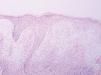

Se realizó biopsia en sacabocados del borde de la zona ulcerada de la lesión (fig. 3). La analítica realizada mostraba elevación de la velocidad de sedimentación globular (VSG) y leucopenia de 4.400/mm 3 con alteración de la fórmula leucocitaria (20,1 % neutrófilos, 54,9 % linfocitos, 23,3 % monocitos, 1,2 % eosinófilos, 0,5 % basófilos). El resto de los parámetros, así como la bioquímica se encontraban dentro de límites de la normalidad.

Fig 3.--Biopsia de la lesión.

La biopsia de la lesión mostraba un intenso infiltrado en dermis compuesto fundamentalmente por neutrófilos con formación de abcesos, junto con prominente edema en la unión dermoepidérmica con despegamiento de la misma, así como necrosis epidérmica en el borde de la lesión.